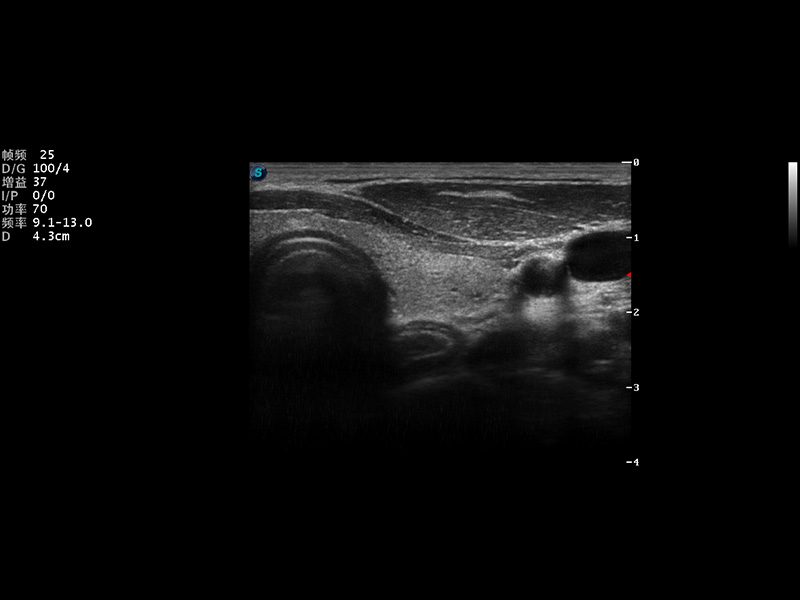

超声彩色多普勒诊断仪

2014年,开立医疗推出了全身应用型超声彩色多普勒诊断仪S22系列,在成像技术、人体工程学设计及工作流优化等方面,以卓越的临床图像、稳定的产品性能、齐全的应用功能充分满足几乎所有的科室的临床诊断需求。